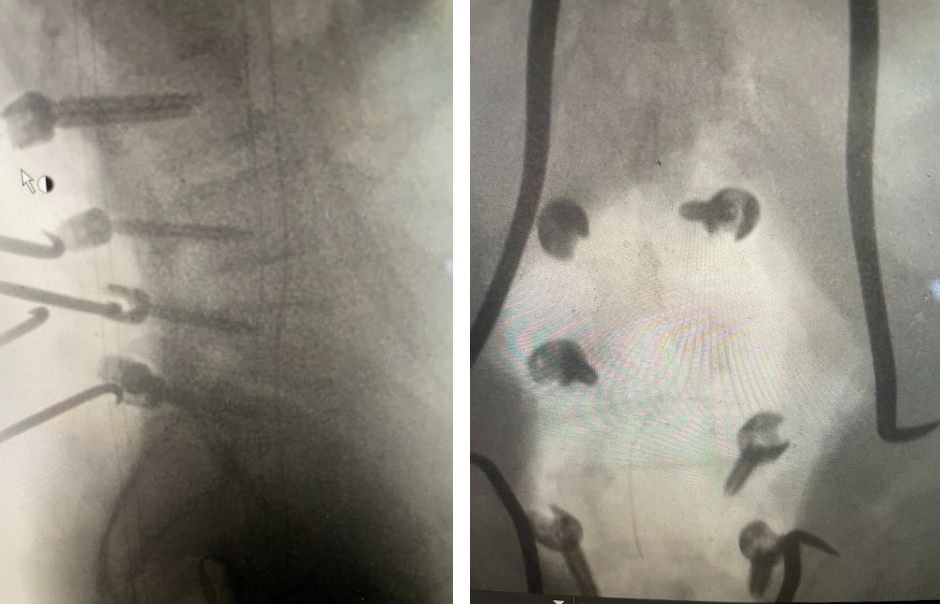

Figure 2. T2-weighted sagittal and axial MRIs demonstrating severe L3-4 stenosis and an L5-S1 grade 1 spondylolisthesis and spondylolysis and L3-4 retrolisthesis. Note the anterior osteophyte formation at L2-3 with attempted autostabilization of segment.

He had mild proximal weakness of his hip flexors. He also had a history of diabetes, hypertension, and hypercholesterolemia. Imaging studies were obtained. Plain x-rays (Fig. 1) demonstrated a degenerative levoscoliosis with the apex of the curve at L2-3. Lumbar MRI (Fig. 2) showed severe degenerative disc disease with an L5-S1 grade 1 spondylolisthesis and a significant retrolisthesis at L3-4 with severe lumbar stenosis.